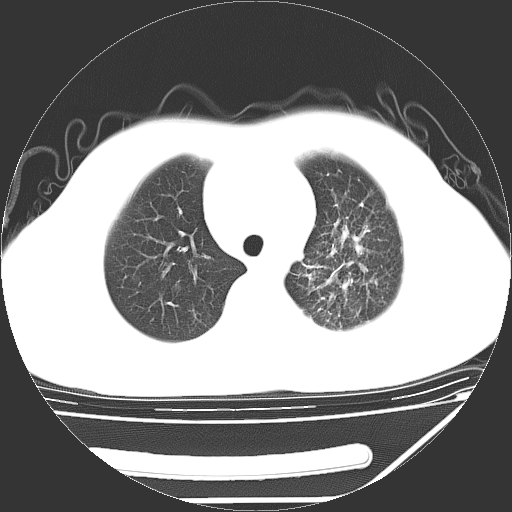

男,13岁,咳嗽、咳痰伴发热一周。

上纵隔课件多枚淋巴结,部分相互融合,左侧支气管壁增厚,肺纹理较右侧增粗,患者,男,13岁,

中上纵隔见多枚淋巴结肿大,部分相互融合成团片,左肺门增大,上叶支气管变窄,肺内多处斑片状 索条状及棉絮状致密影。临床“男,13岁,咳嗽、咳痰伴发热一周。”首先考虑:原发综合征!不除外淋巴瘤可能!

中上纵隔见多枚淋巴结肿大,部分相互融合成团片,左肺门增大,上叶支气管变窄,左肺支气管血管束增粗,可见磨玻璃样影。临床“男,13岁,咳嗽、咳痰伴发热一周。”首先考虑:淋巴瘤可能性大!